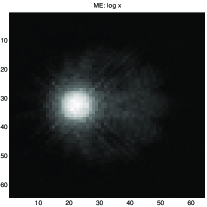

Fig. 8 shows results obtained in X-ray tomography image reconstruction. In this figure a) shows the original image, b) shows the projections (data), c) shows the backprojection reconstruction, d) shows a reconstruction using a Gaussian prior, e) shows a reconstruction using a Gamma prior, and f) shows a reconstruction using GNC with truncated quadratic regularization.

|

|

|

| a | c | e |

|

|

|

| b | d | f |

a) original, b) projections (data), c) Backprojection, d) Gaussian reconstruction, d) Gamma prior reconstruction, and e) GNC reconstruction